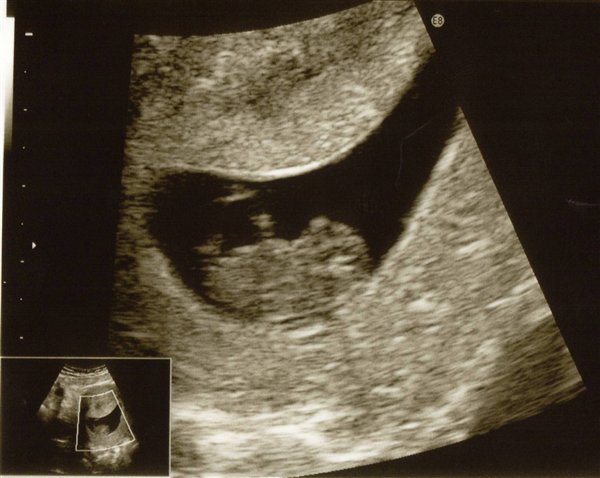

jeg er 9 + 1 uger henne. vil gerne have kønnet at vide når jeg kan. Var til NF i onsdags da jeg troede jeg var 12 uger henne, men niksen det var hun ikke. så nu skal jeg afsted igen d. 2 November

Lige et billede af bønnen